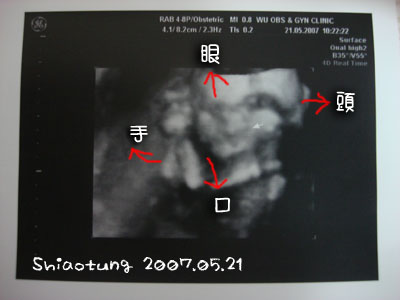

這骷顱頭就是李豬豬的上半身側面,

只有大頭和手彎曲在那邊,

不知道在禱告什麼?

因為都還沒長什麼肉,

所以看起來都是骨頭一截一截的。

家裡的人都看沒有,

但是我看起來還挺明顯的,

可能這張照片比較模糊,

拿遠一點看就很像啦!